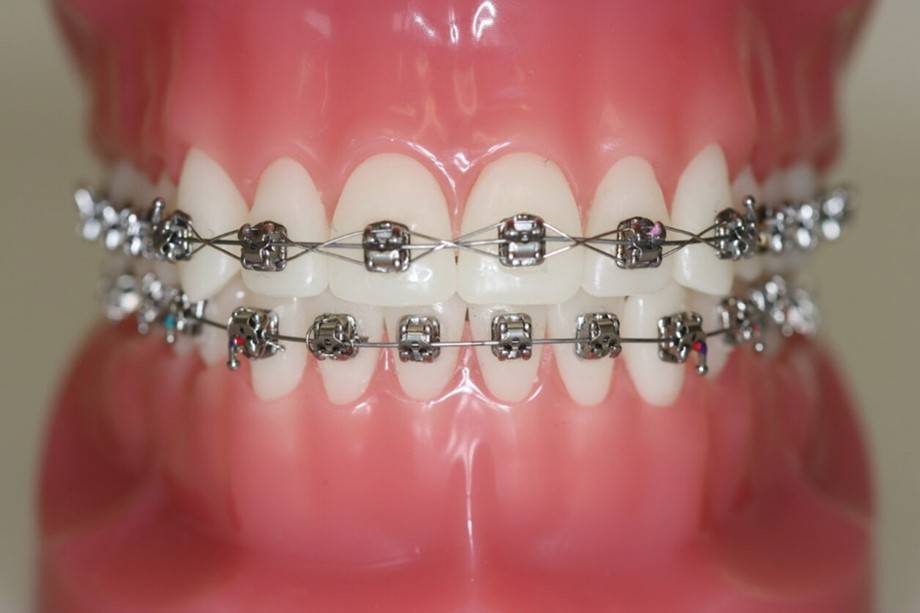

Fastsiddende bøjler

Brackets eller ”togskinner” bliver limet fast på tænderne. Oftest er det nødvendigt med fastsiddende bøjler i både overkæben og underkæben.

Det kan tage op til en uge at vænne sig til faste bøjler eller "brackets". Tænderne vil være ømme de første 2-3 dage, og det kan være rart med mad, der ikke skal tygges for meget.

Nogle har brug for almindelig smertestillende.

I starten kan der opstå en lille blæne eller et lille sår i slimhinden. Du får voks med hjem til at sætte på dine bøjler.

For at undgå at bøjlen går i stykker eller bliver løs, er det vigtigt, at du ikke spiser hårde og seje fødevarer som f. eks. karameller, vingummi, lakridser, bolsjer og slikkepinde.

Hårde madvarer som f.eks. gulerødder, æbler og pærer skæres i mindre stykker.

Det er vigtigt, at du børster tænder og bøjler grundigt rene morgen og aften. Ellers er der risiko for tandkødsbetændelse og skader på tænderne - eller i værste fald huller i tænderne.

Du får et tandbørstesæt udleveret sammen med en grundig instruktion, inden du forlader klinikken.

Vi tjekker altid din tandbørstning ved hvert kontrolbesøg.

Hvis vi ser, at der er begyndt at ske skader på dine tænder, kan vi være nødt til at afbryde behandlingen før tid.